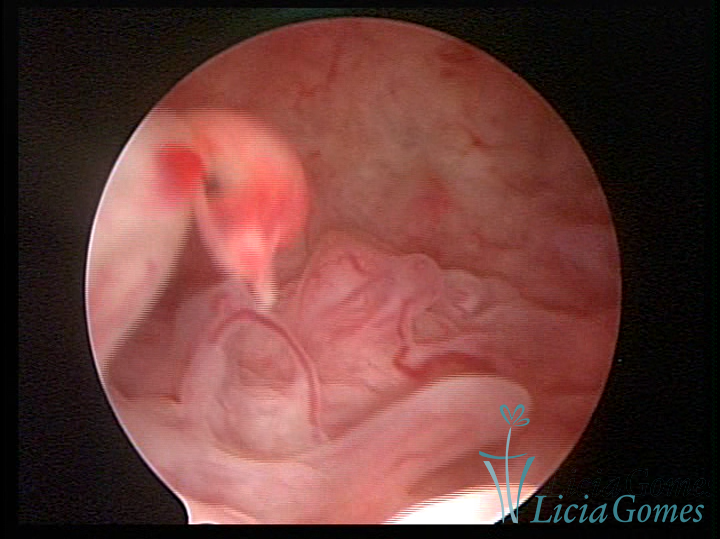

Este pode apresentar uma gama variável de aspectos macroscópicos, com aspecto pseudopolipoide; lembrando tecido cerebroide ou com reação deciduoide;a vascularização superficial é mais evidente e com vasos em formatos de saca-rolha ou espirais visualizando também a vascularização com atípias, com aumento do calibre dos vasos superficiais, pode ser encontrado também tecido em necrose, poderá haver um pequenos dendritos (papilomatoso).